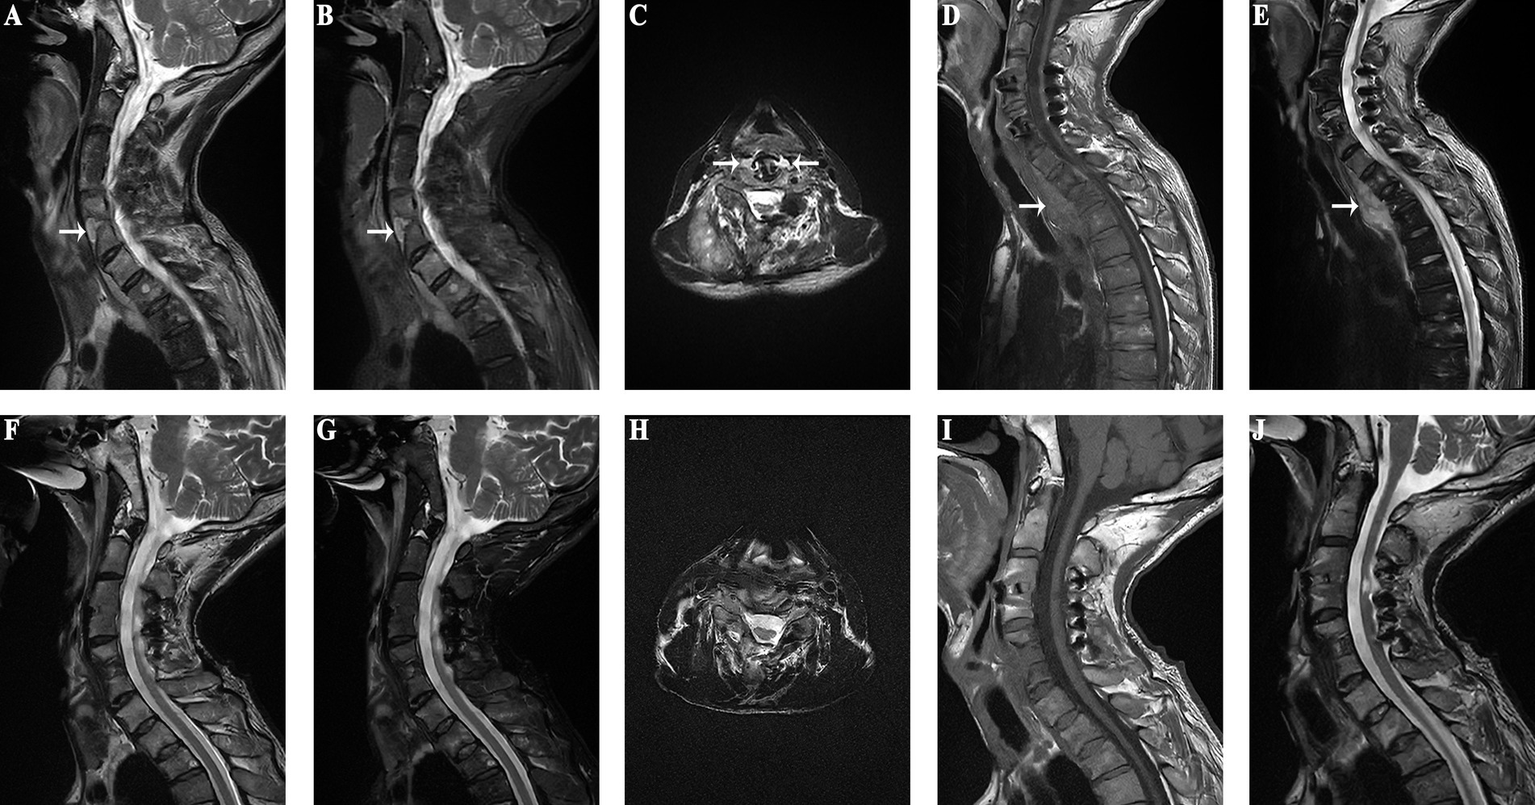

An adult patient was paralyzed due to quadriplegia from trauma and underwent C3/4 and C5/6 ACDF, TN, along with posterior cervical single-door surgery. Although the limb function was significantly improved postoperatively, at 5 years postoperatively the patient developed worsening neck and shoulder pain with recurrent fever, suggestive of a cervical esophageal perforation. Four months of antibiotic treatment resulted in no improvement. Upon admission to our hospital, imaging revealed bone resorption around the C5 and C6. Given the clinical suspicion of an esophageal perforation, the patient was admitted for anterior cervical surgery. Because of the intermittent fever, low protein, and elevated inflammatory markers, nutritional support was initiated. Subsequent investigations, including MRI, esophagography, gastrointestinal endoscopy confirmed an esophageal perforation. MRI suggests mass in front of C5/6 vertebral body (Figures 3A–C), and abnormal signal in front of C7 to T2 vertebral bodies suggests potential mediastinal infection (Figures 3D,E). After stabilizing the patient’s condition, surgery revealed significant vertebral body absorption and esophageal rupture. Internal fixation removal (C5/6), esophageal repair, and sternocleidomastoid muscle flap occlusion were performed. Postoperative follow-up MRI shows that the inflammatory mass in front of the cervical spine has resolved (Figures 3F–H). Follow-up MRI performed 1 month postoperatively showed resolution of the mediastinal abnormalities (Figures 3I,J), and the patient remained asymptomatic with no abnormal imaging findings at 1 year postoperatively.

Figure 3

(Case 4) (A–C) An inflammatory mass anterior to the C5/6 vertebrae is observed preoperatively (as indicated by the white arrow in the diagram). (D) MRI of the thoracic spine reveals low signal intensity anterior to the C7-T2 vertebrae on T1-weighted images (as pointed by the arrow in the diagram). (E) MRI of the thoracic spine shows high signal intensity anterior to the C7-T2 vertebrae on T2-weighted images (as indicated by the arrow in the diagram). (F–H). Postoperative MRI shows no inflammatory mass in front of the cervical spine. (I) Resolution of the low signal intensity anterior to the C7-T2 vertebrae on T1-weighted images. (J) Disappearance of the high signal intensity anterior to the C7-T2 vertebrae on T2-weighted images.